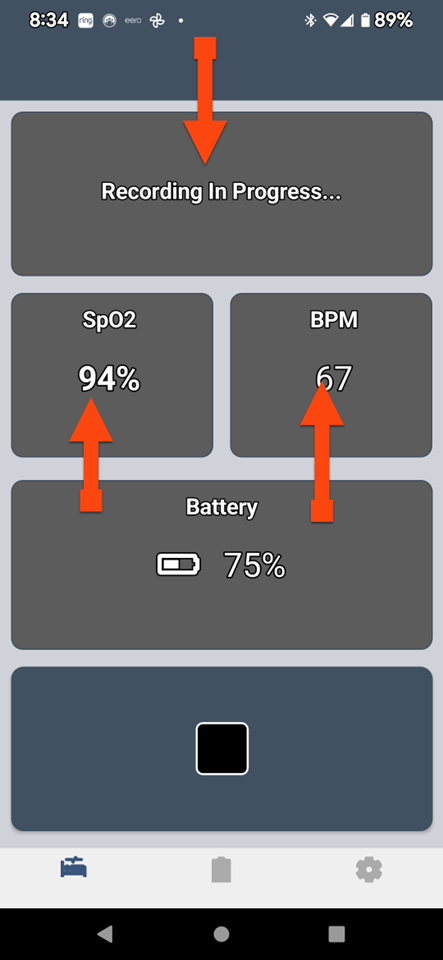

SLEEPIMAGE APP (Android)

SLEEPIMAGE APP (Android)

SLEEPIMAGE APP (Android)

SLEEPIMAGE APP (Android)

SLEEPIMAGE APP (Android)

SLEEPIMAGE APP (Android)

SLEEPIMAGE APP (Android)

SLEEPIMAGE APP (Android)

SLEEPIMAGE APP (Android)

SLEEPIMAGE APP (Android)

SLEEPIMAGE APP (Android)

SLEEPIMAGE APP (Android)

SLEEPIMAGE APP (Android)

SLEEPIMAGE APP (Android)

SLEEPIMAGE APP (Android)

SLEEPIMAGE APP (Android)

SLEEPIMAGE APP (Android)

SLEEPIMAGE APP (Android)

SLEEPIMAGE APP (Android)

SLEEPIMAGE APP (Android)